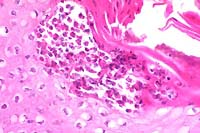

- Case IV - N97-136 (AFIP 2642346)

- Signalment: Young adult, mixed breed, male, canine.

- History: This animal appeared normal until the second

week of July when hair loss and foul-smelling skin were noted.

Skin scrapings did not reveal any agent, but mange was suspected.

There was no improvement after ivermectin treatment, and the

Gross Pathology: The hair coat was thin over large portions

of the carcass, especially the flank, ventrum, axilla, groin,

and around the ears. Both ears had moderate crusting along free

borders.

- Contributor's Diagnosis and Comments: Moderate to

severe, chronic, locally-extensive dermatitis with intralesional

mites. Etiology: Sarcoptes scabiei var. canis.

- Multiple sections of skin from various body sites, including

the ears (section submitted), have changes ranging from acanthosis

with increased layers of surface keratin (orthokeratotic hyperkeratosis)

to focal zones of parakeratosis and cellular crusts. Moderate

numbers of bacterial colonies admixed within keratin can be seen

over the skin surface, as well as within a few of the keratin-plugged

hair follicles. The stratum corneum of the auricular skin has

various stages and sizes of mites (200-400um) consistent with

Sarcoptes sp. Inflammation within the subjacent dermis is mild

to moderate and consists of eosinophils and mast cells, with

fewer plasma cells and occasional macrophages. There is moderate

dermal fibrosis. The previously described inflammatory cells

occasionally surround other adnexal structures (apocrine glands

and sebaceous glands).

10x

obj

- Case 13-4. Skin. A serocellular crust overlies the

cross section of the mite. There is marked thickening of the

stratum spongiosum and corneum (acanthosis), intracellular edema

of corneal keratinocytes (hydropic degeneration), and a brisk

inflammatory infiltrate in the papillary dermis.

40x

- Case 13-4. Note the subcorneal microabscess filled

with viable and degenerate eosinophils and neutrophils. The surrounding

keratinocytes are undergoing hydropic degeneration.

- AFIP Diagnosis: Haired skin, pinna: Dermatitis, eosinophilic,

mastocytic, lymphocytic, and plasmacytic, chronic, diffuse, moderate,

with hyperkeratotic crust, intracorneal microabscesses, epidermal

and follicular hyperplasia, parakeratotic and orthokeratotic

hyperkeratosis, and intracorneal mites, mixed breed dog, canine,

etiology consistent with Sarcoptes scabiei var. canis.